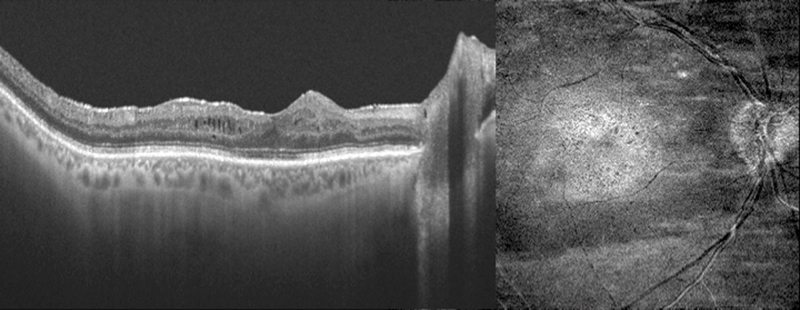

La presencia de fluido subretiniano submacular (

Figura 3 y

Figura 4) y su relación con un mal resultado funcional fue explorado con OCT por primera vez por Wolfensberger

et al.9. A partir de esta serie, otras muchas

10-17 encontraron lo mismo. Sin embargo, otros estudios fallaron en encontrar esta relación

18-21. Todos estos estudios tienen en común el uso de TD-OCT para la evaluación de la anatomía macular, lo que explica la disonancia en los resultados, ya que aunque la TD-OCT es capaz de detectar la presencia de FSR, no es tan precisa para delimitar los cambios en la retina externa

22.

En conclusión, la influencia del FSR en la agudeza visual postoperatoria es, cuanto menos, controvertida.

Figura 3. Múltiples burbujas de fluido subretiniano (Topcon 3D 2000 SD-OCT).

Figura 4. Membrana epiretiniana y fluido subretiniano subfoveal (Zeiss Cirrus SD-OCT).